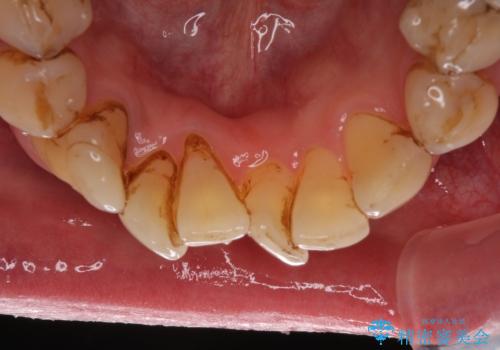

- 前歯のデコボコや、奥歯を咬んだときに痛みがあるとのことで来院された患者様です。

全体的に問題が多く、全てをしっかりと治療したいとのことでした。

全体的に中等度の歯周病と診断されたため、歯周外科処置やインプラントによる咬合回復から進めて行き、矯正治療による歯列改善を行った後にオールセラミッククラウンにて補綴することとしました。

矯正治療を希望して来院されましたが、歯周病を併発していたため、矯正治療開始前の処置が非常に多くなりました。特に歯槽骨の再生治療を行ったため、外科処置後の静置期間が長くなり、4年弱の治療期間となりました。